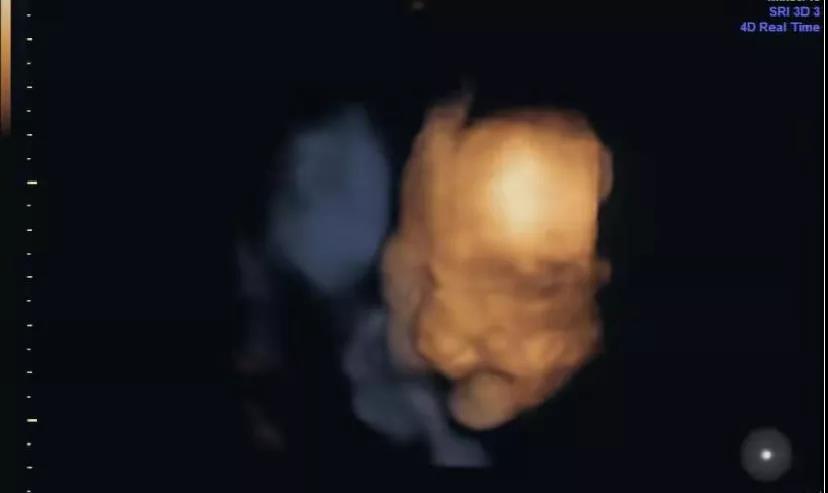

怀孕27周时

做四维彩超查出宝宝唇腭裂

好不容易约上的四维

个晴天霹雳的消息向我丢来

宝宝有唇腭裂问题

四维查出宝宝左侧唇裂2.5mm

牙槽突裂2.7mm

日渐成熟的超声诊断技术(四维彩超)

已成为降低新生儿出生缺陷率的重要途径

超声影像(四维彩超)

重要的价值是排畸

其次才是看胎儿在宫内的情况

它能够多方位、多角度地

观察宫内胎儿的生长发育情况

并为早期诊断胎儿是否存在

先天性体表畸形和先天性心脏

等疾病提供准确的科学依据。